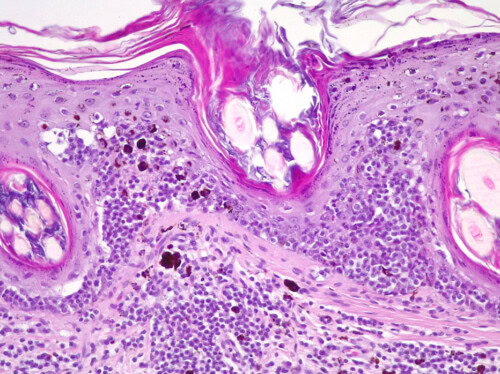

L’examen histopathologique de biopsies cutanées montre une infiltration tumorale de la partie basse de l’épiderme ainsi que du derme par de cellules lymphoïdes de taille moyenne. L’intensité de l’infiltrat efface les annexes sébacées. Ceci permet de confirmer le lymphome cutané épithéliotrope à moyenne cellules.

Un immunophénotypage confirmera que ces cellules sont bien des lymphocytes T (CD3+ et CD20 -). L’index de proliferation Ki67 est estimé à 5% sur les biopsies transmises.

Photo 6 : examen histopathologique de biopsies cutanées (HES, x 200 ) Epithéliotropisme des cellules lymphoïdes tumorales